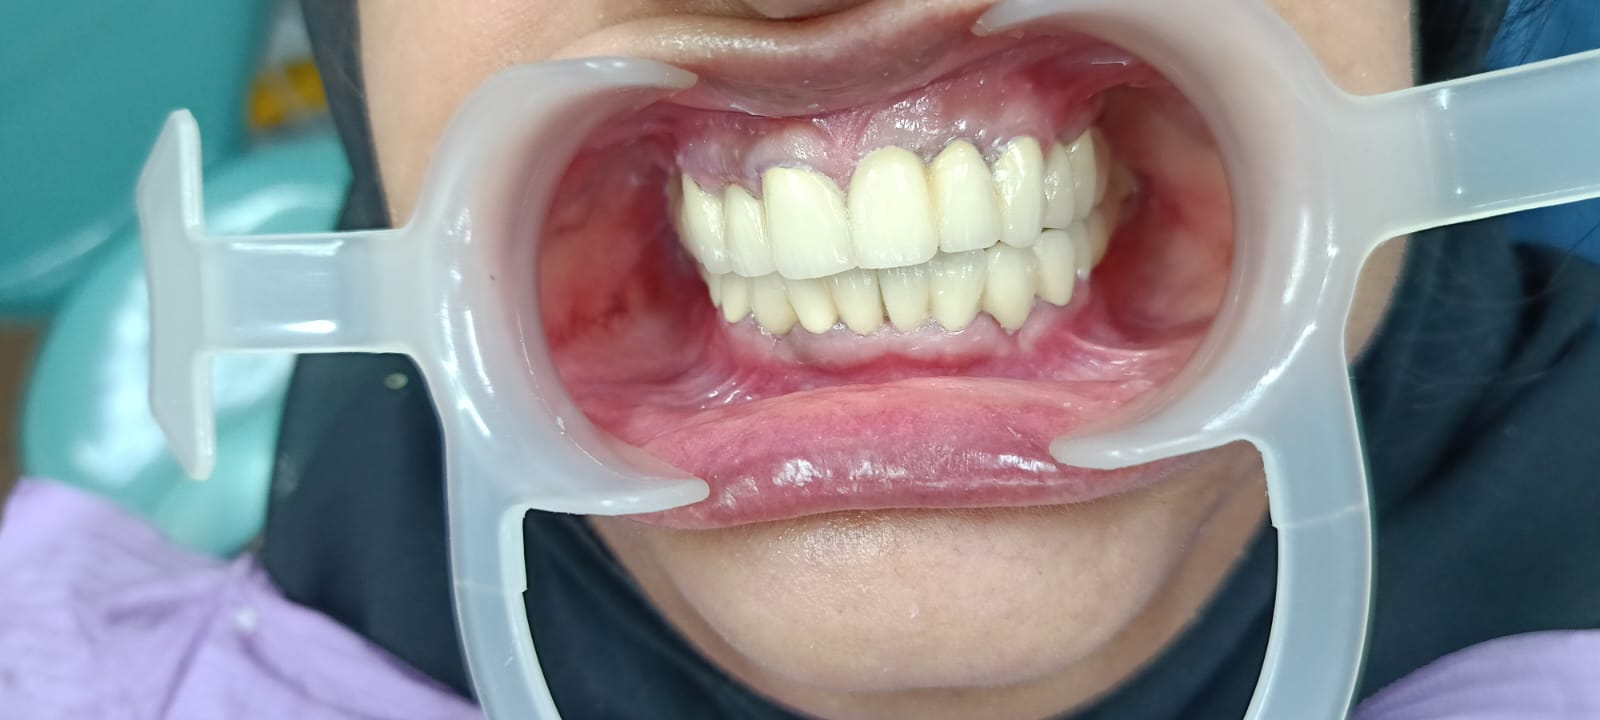

After